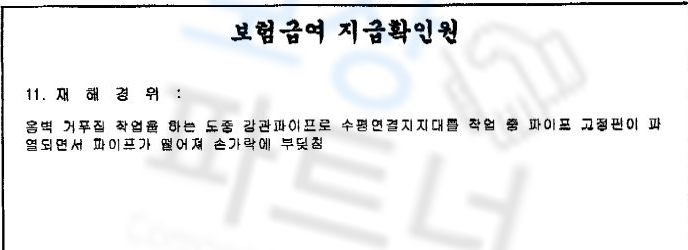

조@@님은 공사 현장에서 자재가 손가락 위로 떨어져 검지손가락이 골절되는 재해를 당하셨습니다. 진단서도 함께 보실까요?

진단서 상의 NOS는 상세불명을 의미하고, 중요한 것은 우측 제2수지 근위지골 개방성 골절 위 진단으로 인해 조@@님은 금속 고정술 즉 핀 고정을 하는 수술적 치료를 받으셨어야 했습니다.